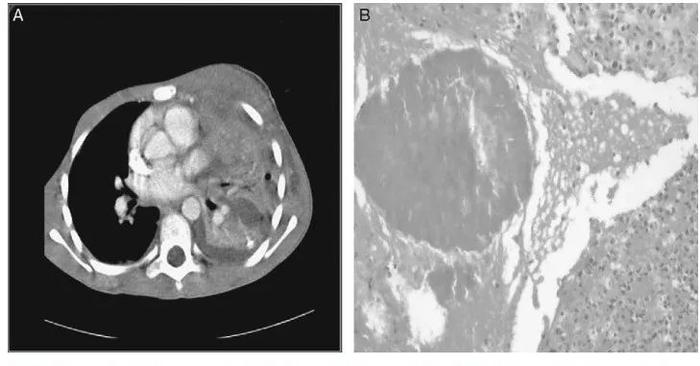

图8 PET-CT扫描肺部放线菌病的影像学表现有时候侵犯胸壁(图9),与肿瘤、结核鉴别困难。

图9 侵犯胸壁

图9 侵犯胸壁5

呼吸系统感染放线菌常常是因为误吸,或是由于颈部、腹腔感染扩散。放线菌容易侵犯胸壁,可导致支气管皮肤瘘(放线菌穿过支气管,突破皮肤),可导致淋巴结肿大,与肺癌、结核鉴别困难。